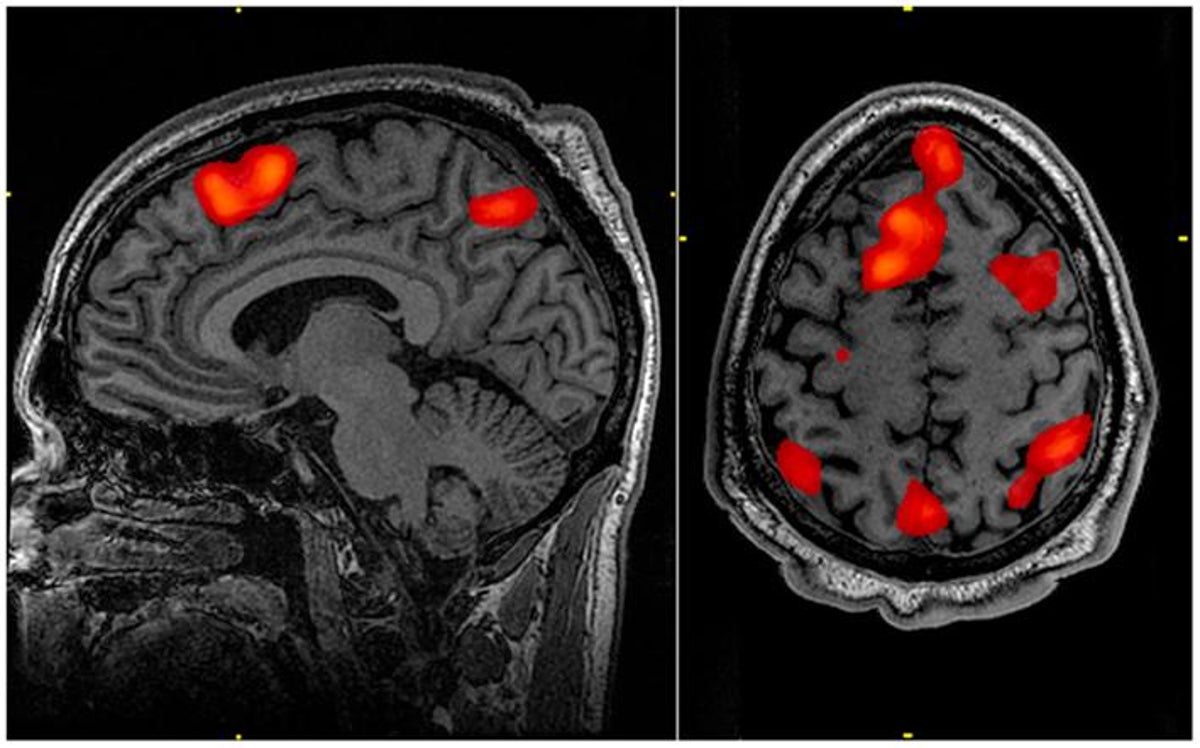

ألقى تخطيط الدماغ الضوء على نحو 900 ثانية من نشاط دماغ الشخص أثناء وفاته، وحاول العلماء التحقق مما حدث على وجه التحديد في 30 ثانية قبل وبعد توقف القلب عن النبض.

وكشفت النتائج أنه بينما كان الشخص يُحتضر، كانت هناك زيادة في موجات الدماغ المعروفة باسم تذبذبات جاما التي تحدث عادةً في أثناء الحلم واسترجاع الذاكرة، بالإضافة إلى تذبذبات دلتا وثيتا وألفا وبيتا.

على سبيل المثال، قال الباحثون إن تذبذبات جاما مرتبطة بوظائف معرفية عالية مثل التركيز، والحلم، والتأمل، واسترجاع الذاكرة والإدراك الواعي، مثل تلك المرتبطة بتذكر الأحداث.

وأوضح العلماء أنه «بالنظر إلى أن الاقتران المتبادل بين نشاط ألفا وجاما متورط في العمليات الإدراكية واسترجاع الذاكرة في الأشخاص الأصحاء، فمن المثير للاهتمام التكهن بأن مثل هذا النشاط يمكن أن يدعم استعادة ذكريات الحياة التي قد تحدث في حالة الاقتراب من الموت».